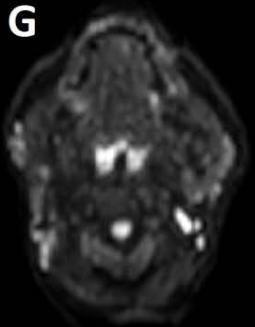

Figure/Patient 3

An 8 year-old girl with prior surgical excision of a right latero-cervical lymphangioma presenting with a new-onset tumefaction within the same region. MRI scans show a 9-10 cm subcutaneous multilocular lesion, extending between two virtual planes crossing the retro-molar trigone and the thyroid respectively, with deep invasion of parapharyngeal spaces cranially and the space between the submandibular gland and the vascular peduncle of the neck caudally. The lesion appears hyper-intense on T2 weighted scans with (A-B) and without (C-D) fat suppression, hypo-intense on T1 weighted scans with (E) and without (F) fat suppression and hyper-intense on DWI scans with high B values (G). Diagnosis of loco-regional recurrence of cystic lymphangioma is done.